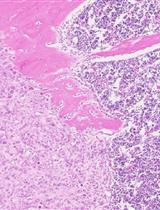

Even though the survival and proliferation stages of cancer cells that have newly settled at a metastatic site are the rate-limiting stages and the most promising targets for drugs, there is a lack of models of the earliest stage of metastasis formation. A method for modeling breast cancer liver metastasis is described here: a stage of transition of a differentiated tumor cell into a cell actively proliferating in a three-dimensional (3D) liver spheroid. Opposite to existing heterocellular 3D models of metastases, the protocol allows modeling the initial stage of liver colonization by metastatic cells, the so-called “micrometastases.” The method includes obtaining a line of fluorescent tumor cells, fluorescence-activated sorting of differentiated cells, preparing a single-cell suspension of liver cells, forming a liver spheroid in an agarose mold, inducing the tumor cell dedifferentiation and proliferation using IL-6, and intravital microscopy of spheroids, with subsequent processing and analysis of fluorescent images in the ImageJ software. The performance of the proposed model was demonstrated using microRNA therapeutics. The ability of a combination of microRNAs to suppress the transition of micrometastasis to macrometastasis in the 3D liver spheroid was confirmed by an immunofluorescent assay of spheroid sections and transcriptome analysis.

In this article, we describe our protocol for modeling the earliest stage of secondary-lesion formation, namely, the transition of a differentiated tumor cell to a cell actively proliferating in a three-dimensional (3D) liver organoid. The model is based on obtaining a line of fluorescent tumor cells, isolating a population of differentiated cells by sorting, incorporating them into a liver organoid, inducing the transition of micrometastasis to macrometastasis by means of IL-6, and analyzing the organoids by intravital microscopy with subsequent processing and analysis of fluorescent images in the ImageJ software.

Validation of the proposed model was performed using miRNA therapeutics. Recently, we proposed a strategy for metastasis prevention with the help of a combination of three miRNAs that inhibit stemness genes, block the dedifferentiation of cancer cells in a metastatic niche, and prevent macrometastasis formation. In the original work, to confirm the efficacy of the combination of miRNAs, via intravenous administration of miRNAs in liposomal form, we conducted a series of experiments indicating the suppression of stemness gene expression, inhibition of mammosphere formation in vitro, and the prevention of metastasis in mice carrying experimental tumors [9]. In the present article, we confirm the ability of the combination of miRNAs to suppress the transition of micrometastasis to macrometastasis in our proposed model of breast cancer metastasis in a 3D liver organoid.